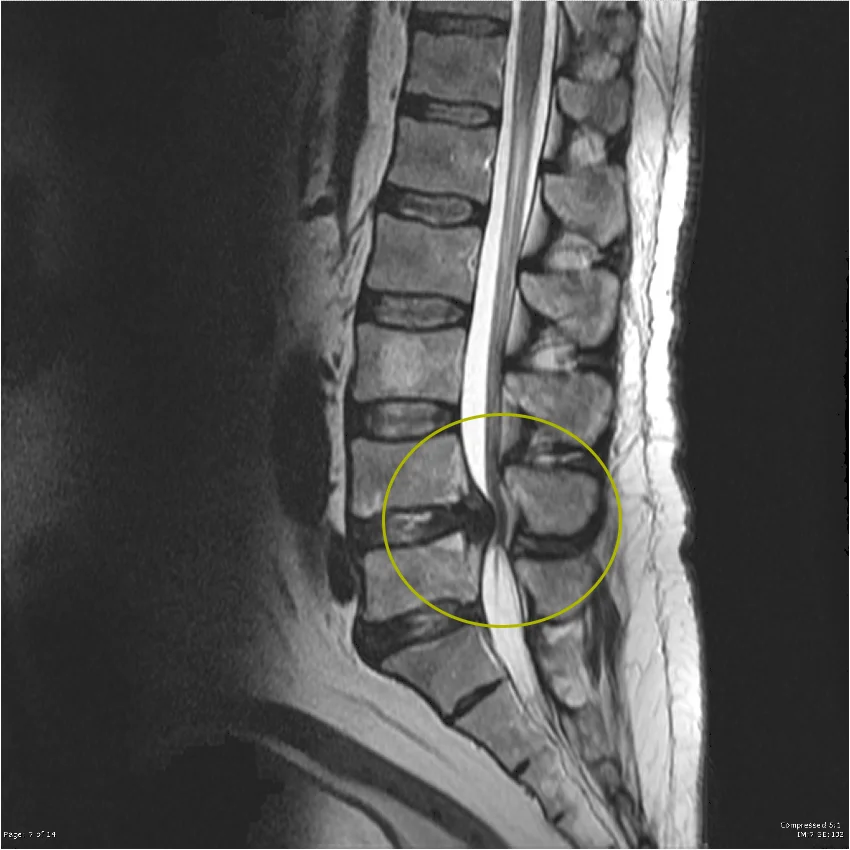

Magnetska rezonancija (MRI) – zlatni standard u dijagnostici

- omogućuje detaljan prikaz mekih tkiva, uključujući intervertebralne diskove, ligamente i živčane strukture

- jasno prikazuje suženje spinalnog kanala, kompresiju leđne moždine ili živčanih korjenova

- pomaže u razlikovanju centralne i foraminalne stenoze

- neinvazivna metoda bez izlaganja zračenju

U kliničkoj praksi, magnetska rezonancija (MRI) predstavlja najvažniju dijagnostičku metodu jer pruža najcjelovitiji uvid u uzrok i opseg stenoze te ima ključnu ulogu u planiranju daljnjeg liječenja.